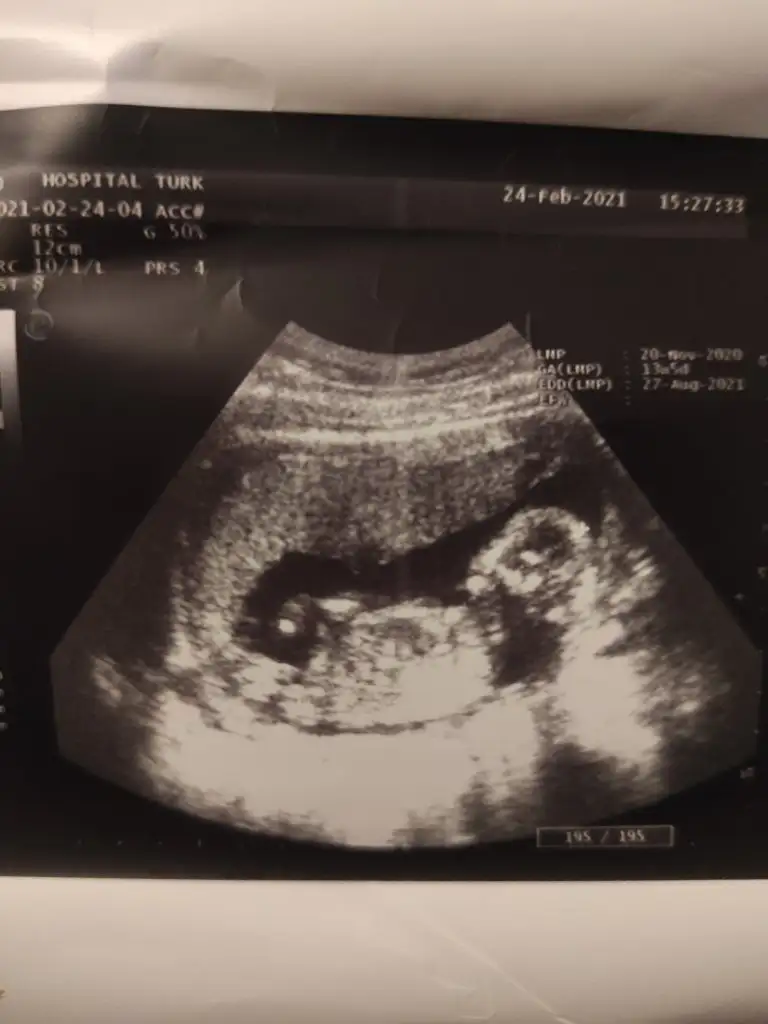

Merhaba,13+5 günlük acaba tahminde bulunabilir misiniz :)